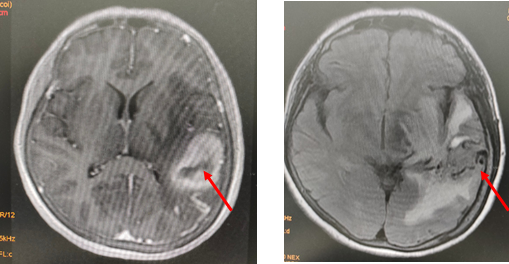

Khối dị dạng xuất huyết nên gây triệu chứng có thể gần giống bệnh lý đột quỵ, may mắn là bệnh nhân không bị tê yếu chi. Bệnh nhân nhanh chóng được các bác sĩ tư vấn chụp mạch máu não kỹ thuật số xóa nền (DSA) để tiến hành can thiệp nội mạch gây tắc khối dị dạng. Đây là một phương pháp điều trị dị dạng động tĩnh mạch não ít xâm lấn bằng đường nội mạch mà Đơn vị can thiệp mạch não - Bệnh viện Trường Đại học Y Dược Cần Thơ đã triển khai điều trị hiệu quả. Sau khi người nhà đồng ý bệnh nhân nhanh chóng được ê kíp TS.BS. Nguyễn Vũ Đằng, Ths.BS Nguyễn Hữu Tài, ThS.BS Trần Văn Đăng (gây mê hồi sức) chụp DSA xác định vị trí động mạch nuôi và gây tắc gần hết, đảm bảo hiệu quả và an toàn cho bệnh nhân.

Hình 2: Hình ảnh khối dị dạng động tĩnh mạch trước can thiệp (A) và sau can thiệp (B)